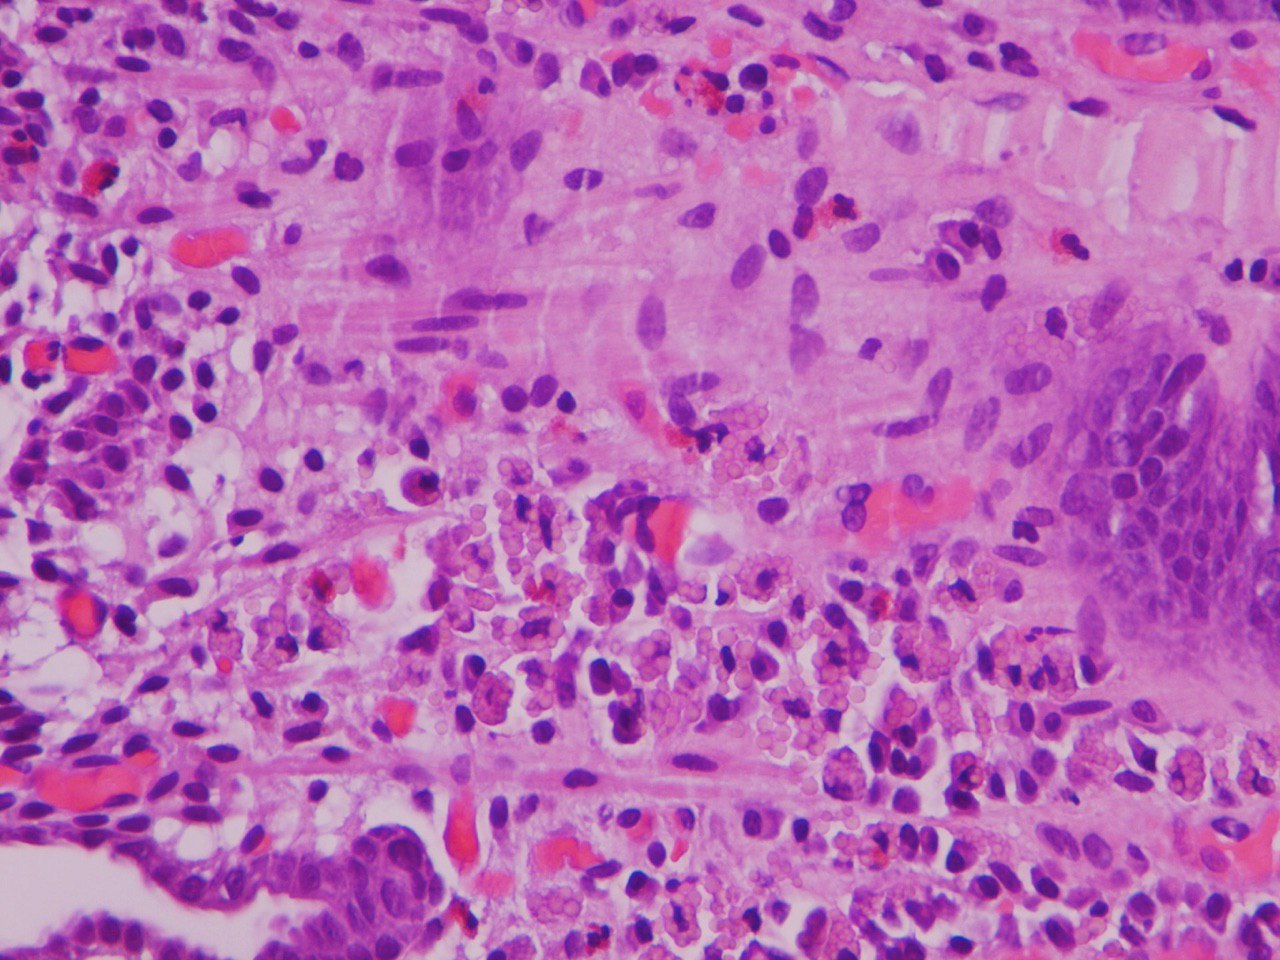

4)В печени, но не печень.... первично желудочная хориокарцинома